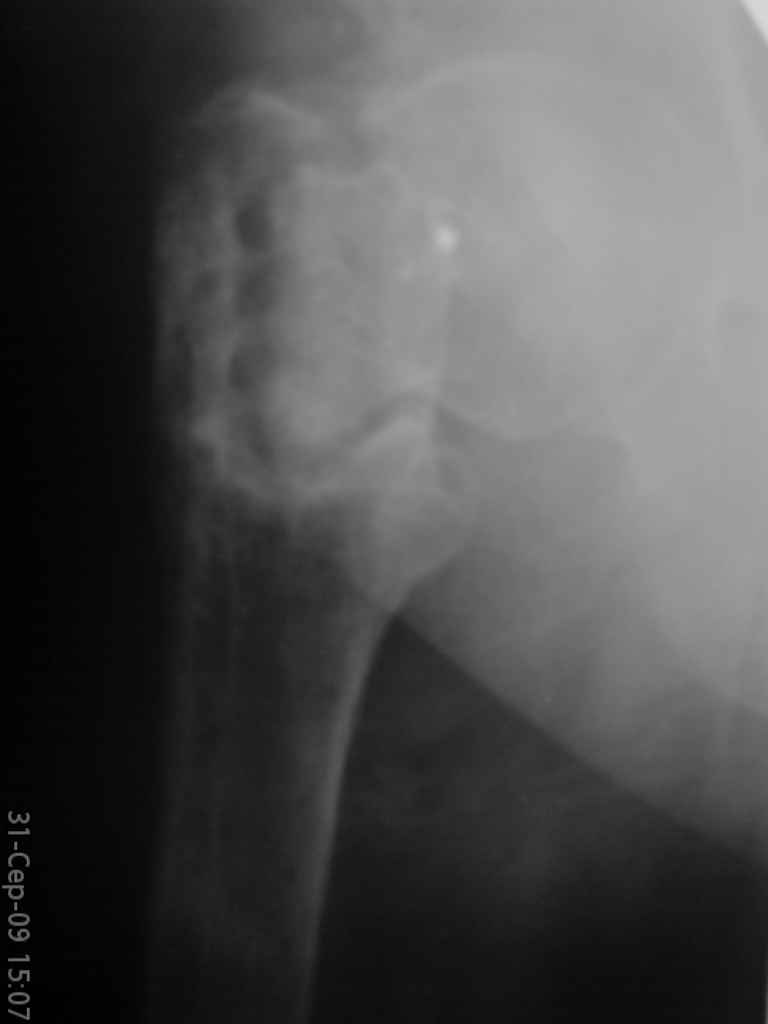

Уважаемые коллеги, помогите определиться с тактикой лечения. Больная, 62 года,жалуется на боли,неопорность левой ноги. Ходит с помощью костылей, укорочение ноги 3 см. Два года назад была оперирована кокой-то накостной пластиной, пластину удалили 4 мес назад. Вопрос такой: предлагать эндопротезирование или делать МОС (что-то по типу стержня Gamma)?За качество снимков извините, по данным МРТ - головка живая

На прошлой неделе оперировали похожего пациента. 2 года после неудачного остеосинтеза PFN в другом регионе. После удаления остатков железа выявилось несращение вертельной области.

В такой ситуации важно устранить варусную деформацию. При использовании гвоздя это непросто. Поэтому в число рассматриваемых

вариантов стоило бы включить вальгизирующую остеотомию с фиксацией 130-градусной клинковой пластиной или DHS.